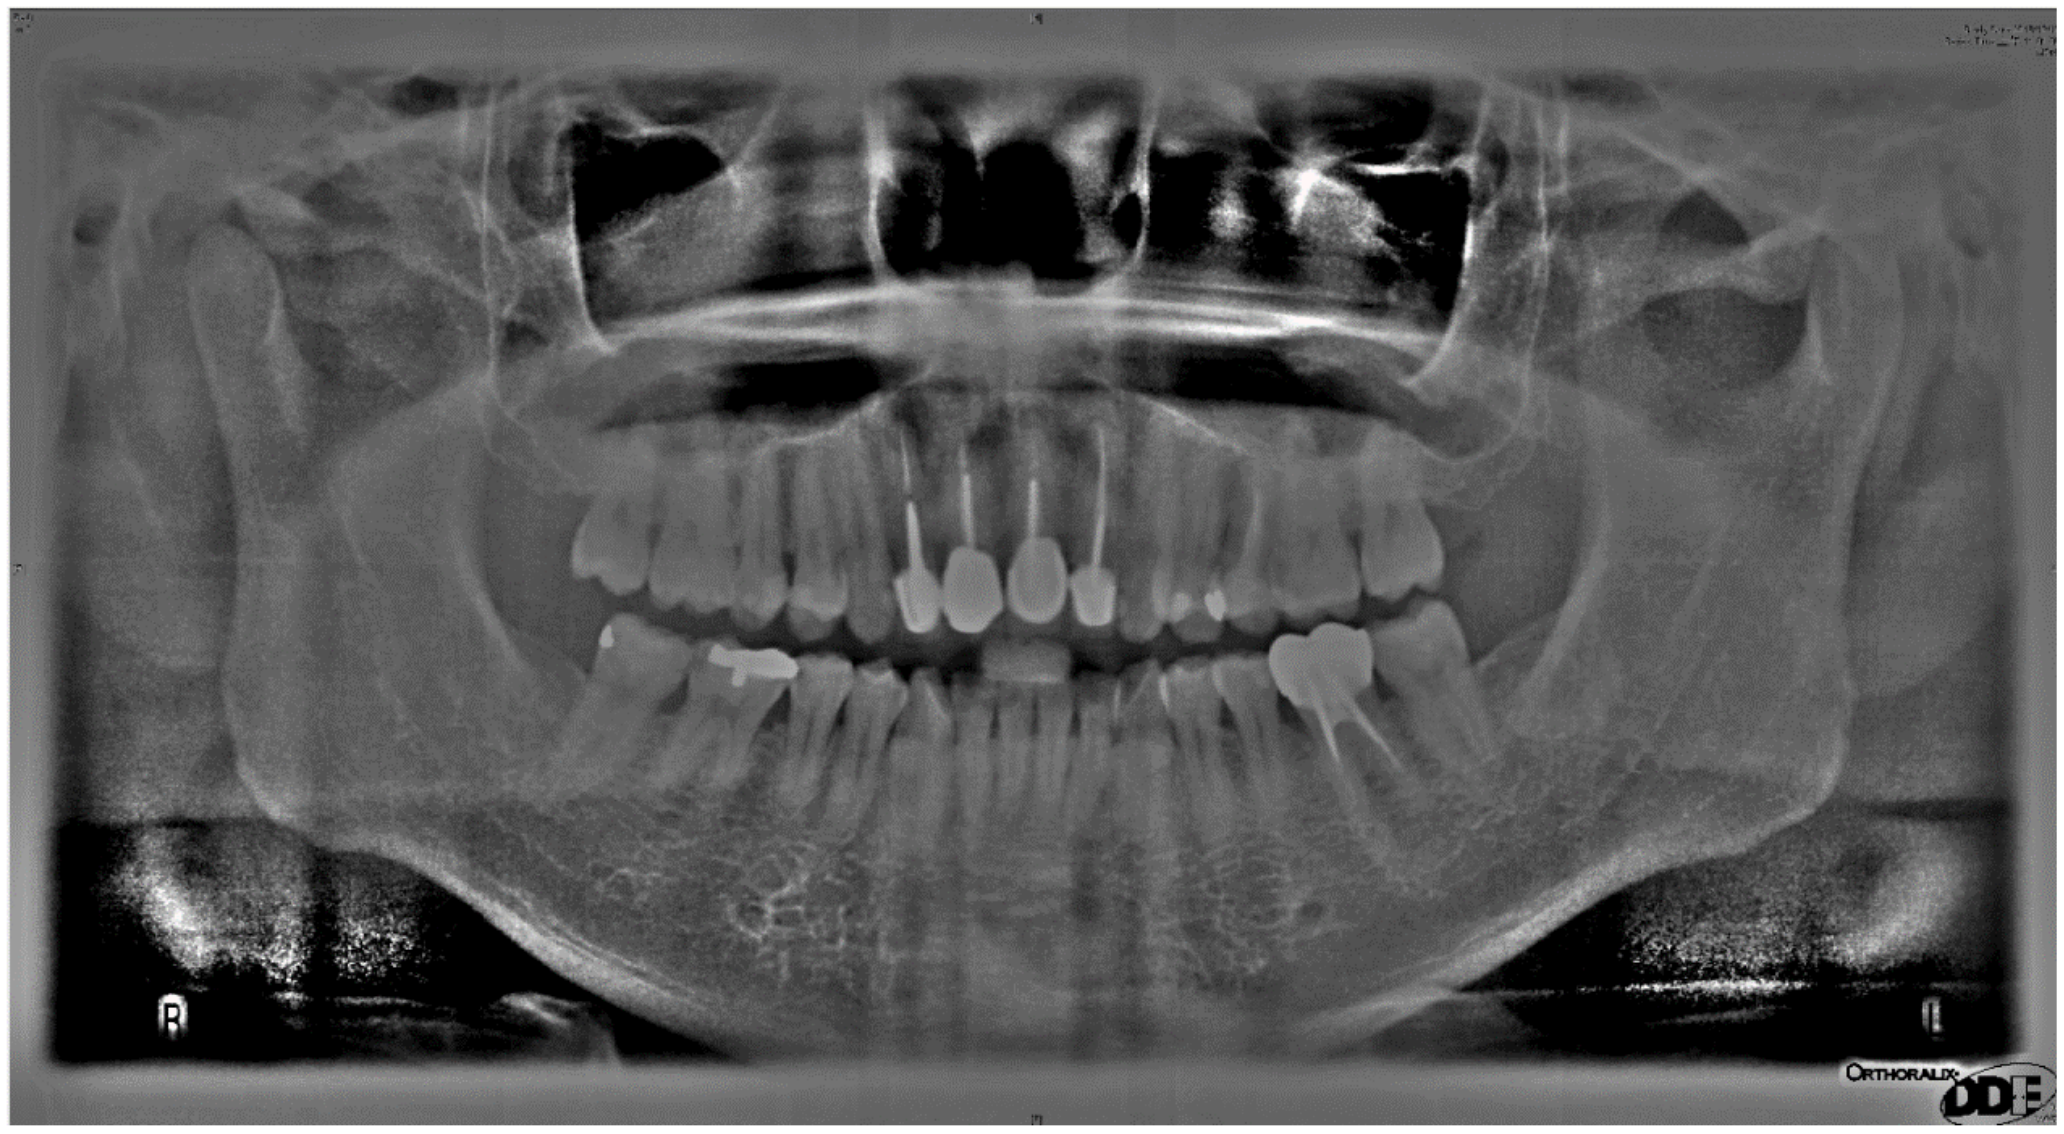

2.1.1. Sharpening

2.1.2. Image Contrast Adjustment

2.1.3. Flat-Field Correction

2.1.4. Adaptive Histogram Equalization

| Image Enhancement in Cutting Accuracy Rate | |||||

| Original Image | Matrix Operation Diagram | Image Contrast Adjustment | Flat-Field Correction | Adaptive Histogram Equalization | |

| Cutting accuracy rate | 34.72% | 51.68% | 58.74% | 78.61% | 89.95% |